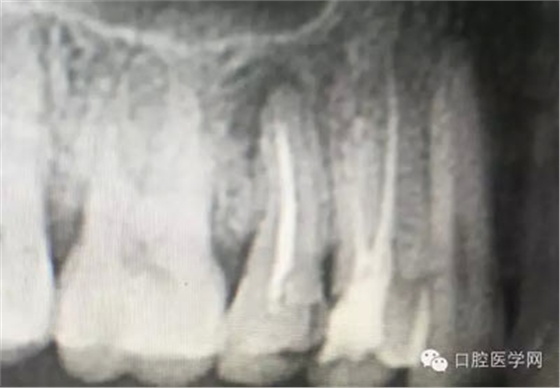

深齲或者是齲壞備洞的時(shí)候意外穿髓,我們?cè)趺刺幚砗眯??后期出現(xiàn)的牙髓的癥狀,是我們操作的問(wèn)題?比如細(xì)菌層的存在,我們沒有清理干凈?還是我們窩洞沒有進(jìn)行消毒,或者是隔濕沒有做好導(dǎo)致的粘結(jié)出現(xiàn)問(wèn)題,還是材料充填的時(shí)手法不對(duì),導(dǎo)致的材料收縮過(guò)大,還是我們的光照設(shè)備出現(xiàn)了老化沒有完全達(dá)到想要的固化,還是懸空的釉質(zhì)沒有去除導(dǎo)致的微滲漏的發(fā)生,或者是材料本身對(duì)牙髓產(chǎn)生的刺激,還是材料選擇的問(wèn)題,或者是我們對(duì)材料的性能和說(shuō)明沒有足夠的了解導(dǎo)致的,沒有按照材料的要求去做,還是我們自身對(duì)牙齒情況的判斷出現(xiàn)的問(wèn)題......